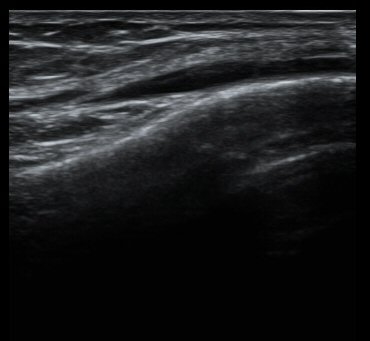

ÃÊÀ½ÆÄ °Ë»ç

´ëÅð°ñ ¿ÜÃø°ú ¾ÕÂÊ Á¾´Ü¸é°Ë»ç¿¡¼­ ¾à°£ÀÇ ¼ö¾×Àú·ù°¡ °üÂûµÊ(±×¸² 1, 2).

¹«¸­ ³»ÃøºÎÀδë Á¾´Ü¸é°Ë»ç¿¡¼­ ³»ÃøºÎÀδë Ç¥Ãþ±ÙÀ§ºÎ Àú¿¡ÄÚ ºÎÁ¾ ¹× ½ÉÃþ±ÙÀ§ºÎ ºÎºÐÆÄ¿­ÀÌ

°üÂûµÊ(±×¸² 3, 4).